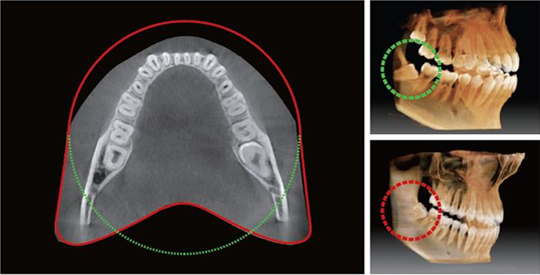

Anatomical FOV, 12x9

Anatomical FOV, 12x9

The innovative FOV of the PaX-i3D Smart provides an arch-shaped volume, which shows a wider view of dentition compared to other devices of the same FOV. Normally, a FOV 10x8.5 image shows tooth #8. However, when the tooth is lying on its side, there is a high possibility that the tooth will be cut out of the image. The "arch-shaped volume" eliminates this possibility and shows the hidden dentition area.